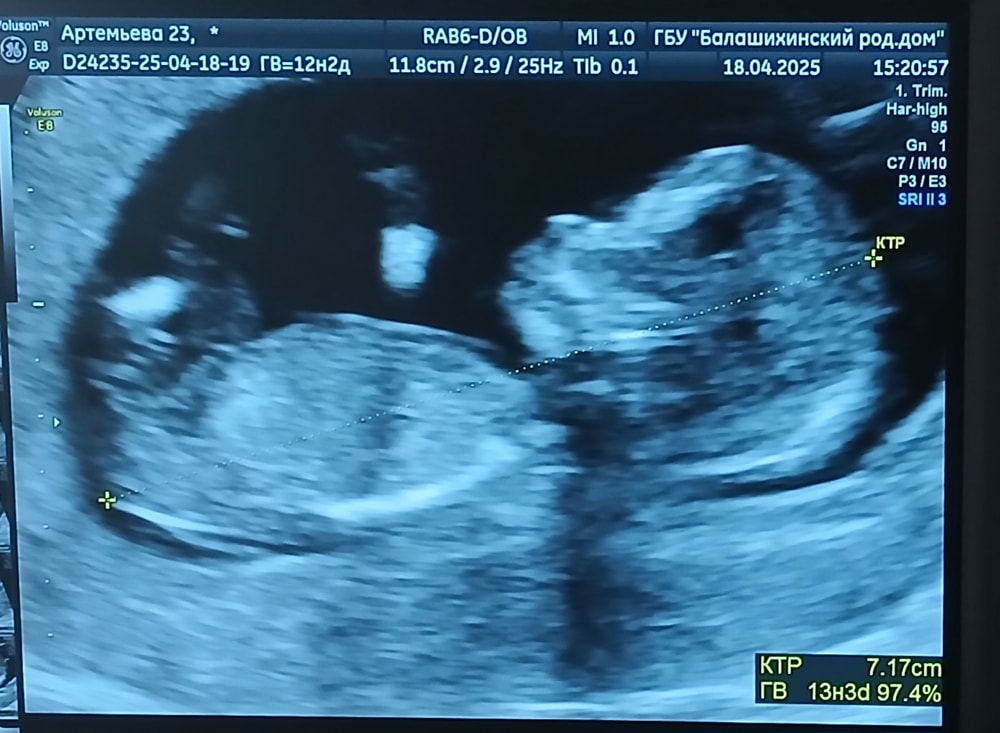

Повторный 1-й скрининг (бесплатный от ЖК)🥰

Анализы, скринингиВсем привет!) Сходила еще раз сегодня на скрининг🥰 мне всё понравилось,было даже лучше видно,чем на платной основе,врач всё в конце объяснила, дала заснять на видео самые удачные моменты😍😍 фоточки две дала самые прекрасные в распечатанном виде, и их же я сфоткала,прикреплю🥹 предположила,что будет мальчик

Я счастлива❤️ Итоговый срок 13 недель + 3 дня

Кажется, действительно мальчик. Ничего себе, какой уже человечище ручками машет 🥰